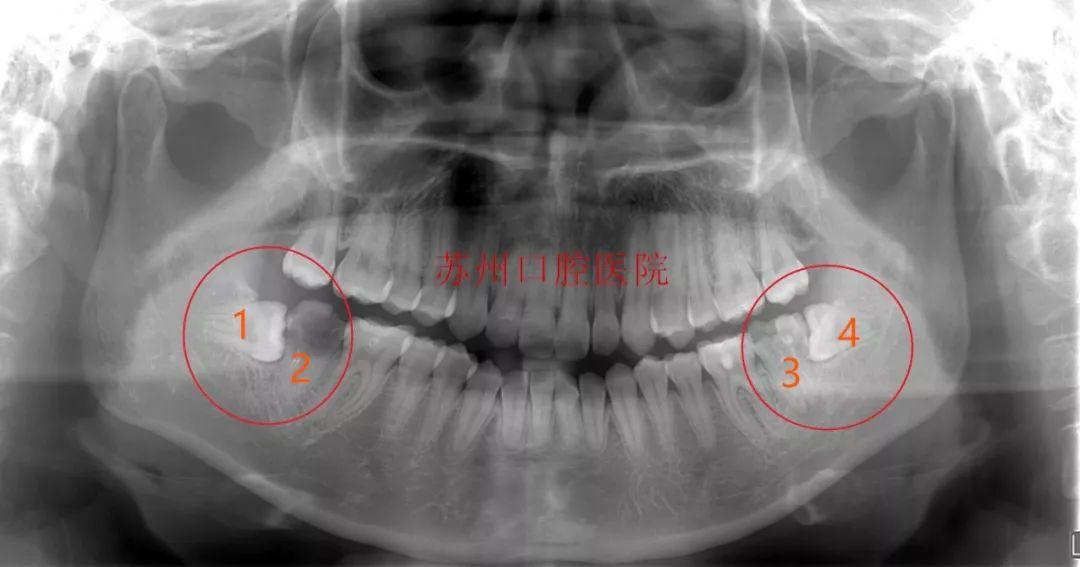

(移植前)

医院牙体牙体牙髓科主任给患者做了检查后,确定患者口内情况:

常规方案是:患者左右下颌都有两颗横位阻生的智齿,没有及时拔除,现在这两颗智齿引起前面7号牙的严重龋坏,按常规调节方案需要拔除两颗智齿,以及智齿前方的两颗7号牙,一共要拔除四颗牙齿,然后再种植两颗牙。

自体牙移植方案:通过预判评估,进行了自体牙移植,在拔除龋坏患牙后,用自身的智齿替代被拔除的患牙行使功能,大限度地保留了天然牙,又避免了种植牙。

(智齿是口腔内牙齿的“佳替补队员”)